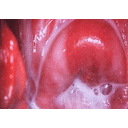

Vaginosis Bacteriana flujo.jpg